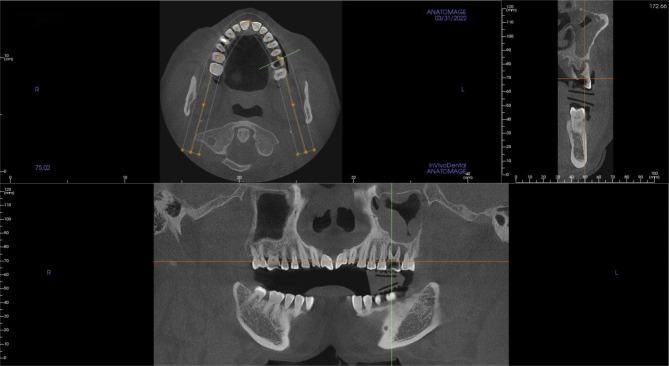

A total of 55 patients with 72 implants placed in the posterior maxillary region with alveolar bone defects were retrospectively analyzed between January 1, 2021, and October 31, 2024. The study was divided into two groups, navigation group and freehand implant group.The preoperative planning implant data and postoperative CBCT data of the actual implant were imported into the dynamic navigation accuracy verification software, and the deviations of the actual implant neck, root, depth and angle were calculated and reported. Clinical indicators including implant deviation, initial stability, implant success were recorded.

There were 38 implants in the navigation group and 34 in the freehand group. All implants were successfully placed without serious complications such as perforation of the maxillary sinus mucosa. The initial stability of the implant in the navigation group was (28.53 ± 5.81)N.cm and (18.47 ± 3.64)N.cm, respectively. The initial stability of the implant in the navigation group was higher than that in the free hand group (P < 0.05). The deviations in the cervical, root, depth, and angulation of the navigation group were all significantly smaller than those of the free-hand implant group, with statistically significant differences (P < 0.05). The median follow-up was 29.6 ± 11.2 months and the implant success rate was 100%.

Immediate implant placement in the maxillary posterior region with bone deficiency assisted by real-time dynamic navigation can achieve good implant accuracy and satisfactory clinical results.